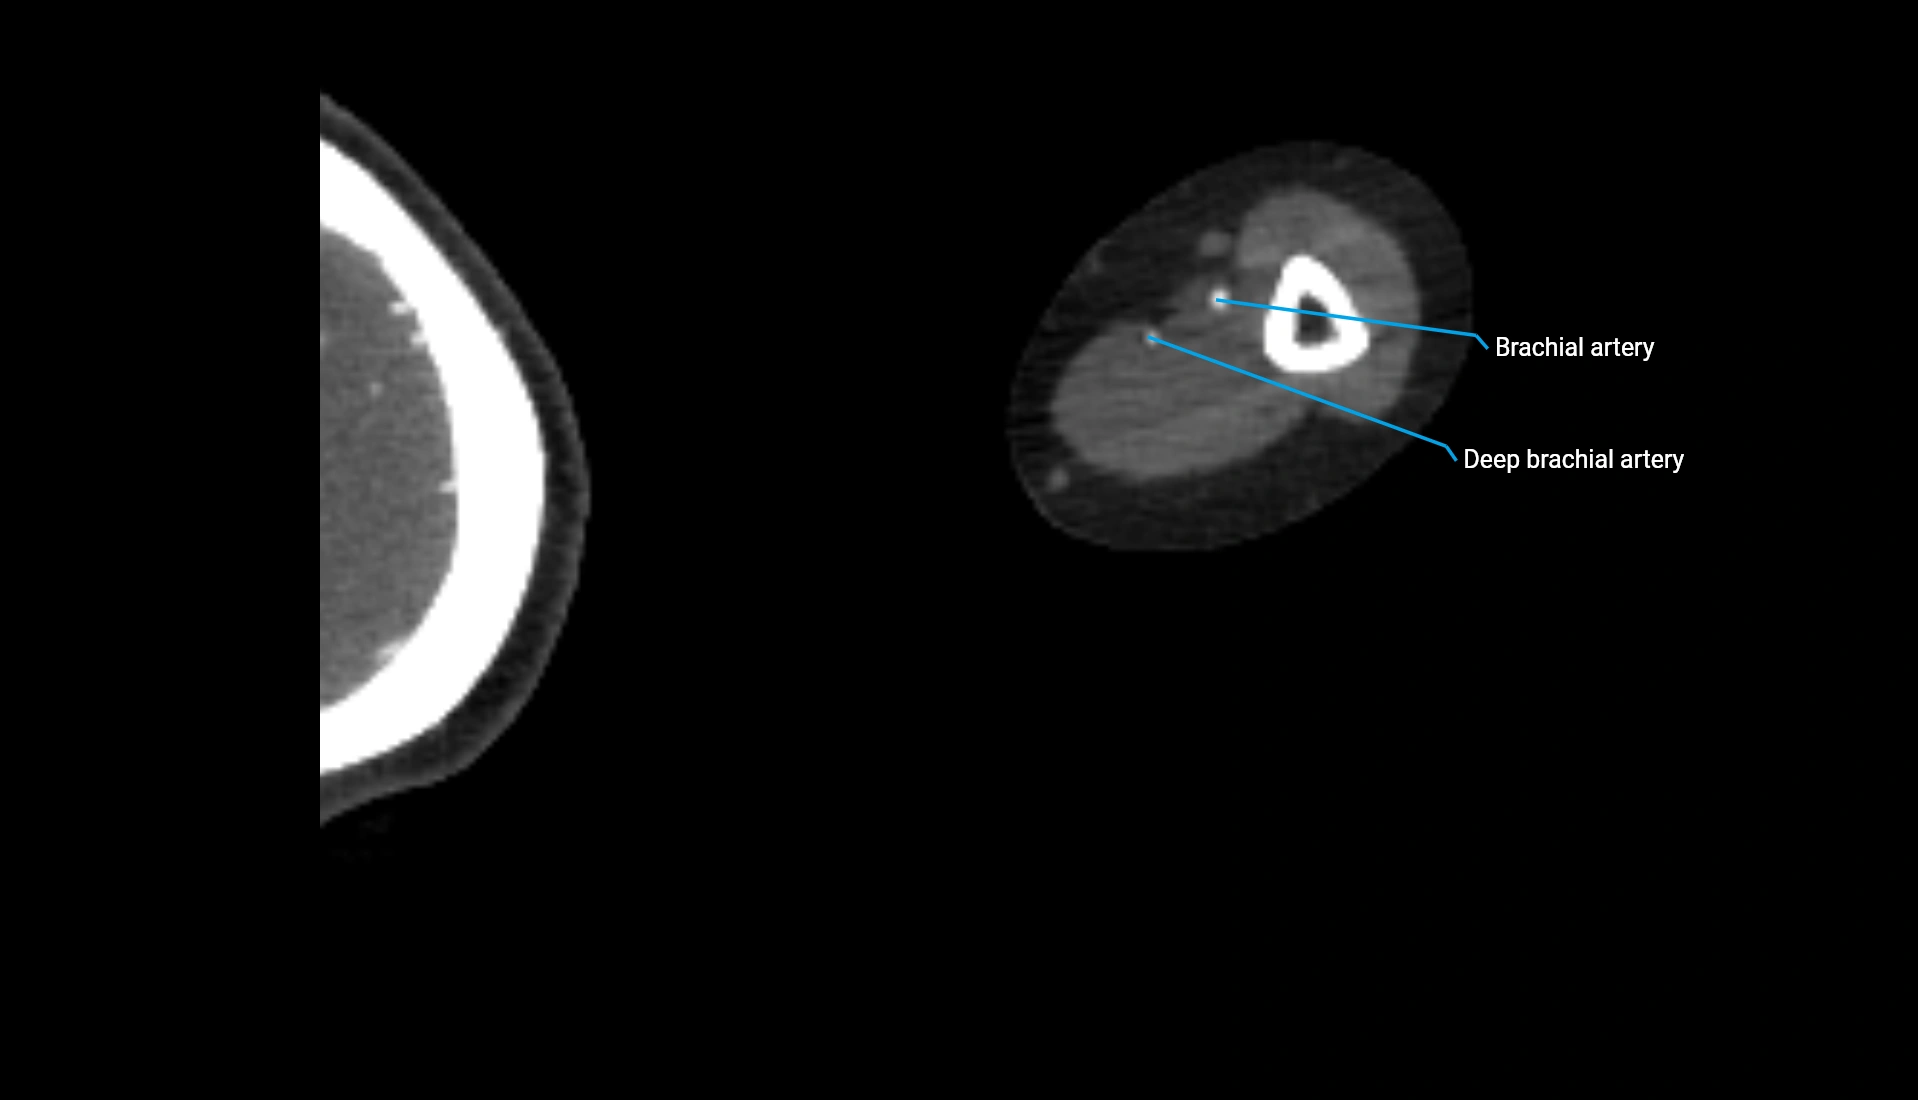

CT Appearance

Non-Contrast CT:

• Cortex: High-density, sharply defined

• Subchondral bone: Dense cancellous matrix

• Articular surface: Smooth concave contour articulating with the capitellum

• Excellent for evaluating bone integrity, alignment, and subtle fractures